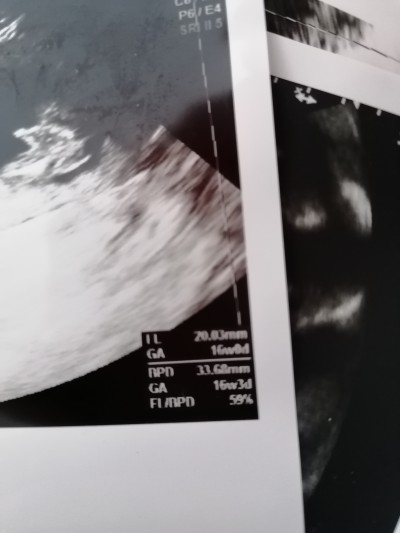

fl 7 ile çarpılınca büyük çıkıyor 16 haftalıkken ki boyu merak ettim kaç yani şimdi boyu

33.68 mm yazan zaten boyu değil mi =/

Canım bu 16 haftalık değer 21 de ayrıntılıys girdiğimde 23 cm dedi 3 cm mi oluyor yani o zaman boyu anlamadım :)

Bunun diğer tarafında AC-FL-BPD falan tek tek alt alta yazan bi yer yok mu.. Orda yazanla hesaplıyorum ben, buralara hiç bakmadım